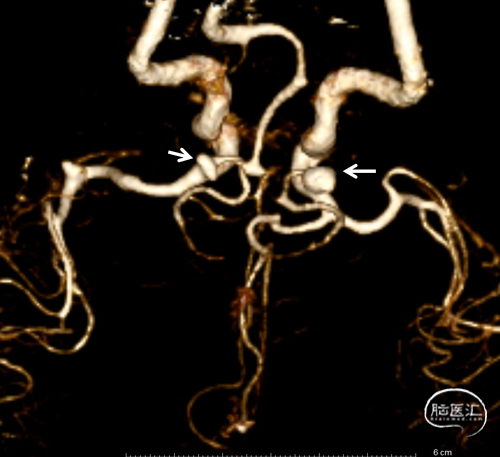

造影:左侧颈内动脉交通段动脉瘤支架辅助栓塞后改变,瘤体内无造影剂泻入,大脑中动脉及大脑前动脉走形正常,显影良好,左侧大脑前动脉A3段可见约2.0mm*1.5mm大小动脉瘤。右侧颈内动脉交通段可见约6.7mm*2.8mm大小动脉瘤,分叶状,瘤颈宽4.0mm,胚胎型大脑后动脉,右侧大脑中动脉M1段可见宽颈梭型动脉瘤,大小约3.9mm×4.6mm。

工作位+路图下Synchro-0.014in×200cm微导丝携带PROWLER SELECT PLUS微导管送至右侧大脑中动脉M2段远端,微导丝携带Echelon-10微导管送至M1段动脉瘤体内。经PROWLER SELECT PLUS微导管释放ENTERPRISE2 4.0mm×16mm,覆盖瘤颈,经Echelon依次填入强生ORBIT GALAXY 3mm×6cm弹簧圈成篮,继续填入ev3 2.5mm×6cm,1mm×2cm,1mm×1cm弹簧圈,造影示M1段动脉瘤填塞完全,造影剂滞留。

调整工作位角度,路图下Synchro0.014×200cmm微导丝携带SL-10微导管送至右侧颈内动脉,再用微导丝携带Echelon-10微导管送至C7动脉瘤瘤体内,经Echelon-10半释放强生ORBIT GALAXY 3mm×8cm弹簧圈,经SL-10释放Neuroform Altas 4.0mm×21mm支架,覆盖瘤颈,继续填塞第一枚弹簧圈,造影示支架位置满意,继续填塞强生ORBIT GALAXY 2mm×6cm弹簧圈,ev3 1mm×3cm,1mm×2cm弹簧圈,复查造影示动脉瘤栓塞致密,载瘤动脉通畅,复查颅内正侧位造影右侧颈内动脉、大脑前动脉、大脑中动脉显影良好。

复查:左侧颈内动脉C7段动脉瘤完全栓塞

右侧颈内动脉交通段可见约6.7mm*2.8mm大小动脉瘤,分叶状,瘤颈宽4.0mm

右侧大脑中动脉M1段可见宽颈梭型动脉瘤,大小约3.9mm×4.6mm,左侧大脑前动脉A3段可见约2.0mm*1.5mm大小动脉瘤。